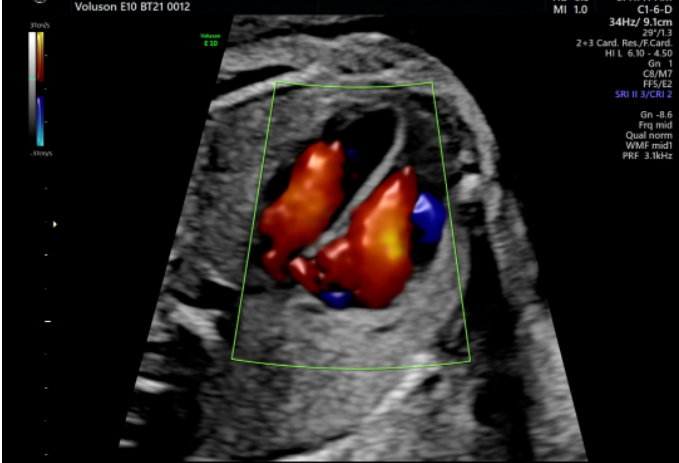

胎儿心脏评估

新生儿心脏畸形是我国新生儿缺陷中高发病率的问题,而超声设备是进行胎儿心脏检查的首要方法。18-24周胎儿心脏只有普通人指甲般大小,所以胎心检查对于超声图像质量及辅助的诊断工具要求非常高。

Voluson系列超声具备一整套领先的胎心成像技术,支持从胎儿心脏结构到心功能的全面分析,是胎儿心脏检测评估领域的技术领导者。Voluson E10的煊光平台配合凸阵电子矩阵探头,提供优异的图像分辨率,能更快地展现胎心结构和功能,双平面成像技术可实时观察胎心结构和血流变化,帮助临床医生及时作出准确诊断。